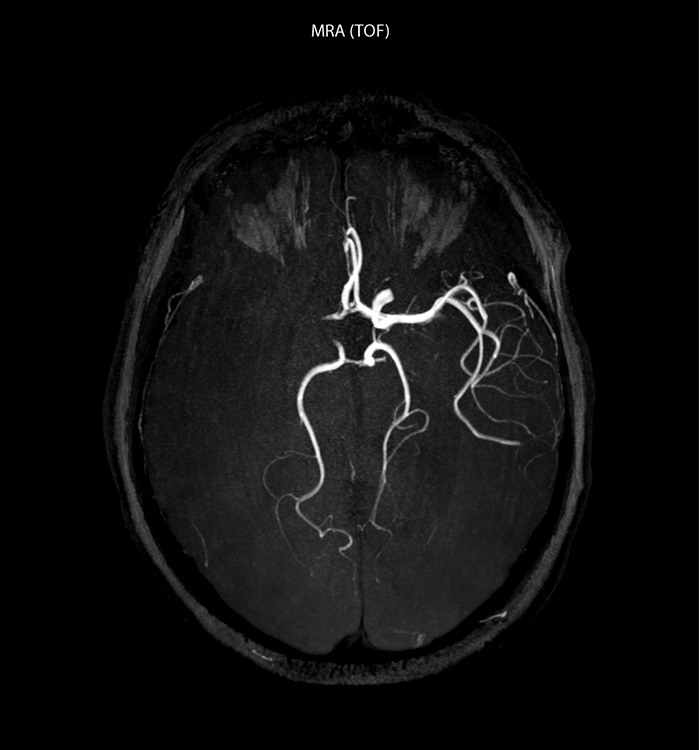

“Every center is different, but for me the ideal protocol for stroke includes diffusion weighted imaging, FLAIR, and fast susceptibility imaging,” says Dr. Savatovsky. “Our fast susceptibility weighted imaging takes 50 seconds, so it’s as fast as T2*-weighted imaging. It visualizes hemorrhage but also the clots. We also do 3D MR angiography that provides information on cervical and brain vessels. If the patient does not need immediate treatment, or if additional information is needed to decide on treatment, we might also add perfusion imaging and post-contrast T1-weighted imaging.”